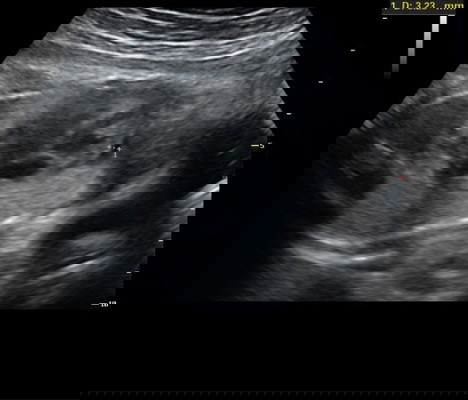

ซาวด์เจอถุงน้ำบริเวณเยื่อหุ้มหัวใจลูก

อายุครรภ์ 8 เดือน คุณหมอซาวด์เจอถุงน้ำบริเวณเยื่อหุ้มหัวใจลูก แต่หัวใจเต้นปกติดี ผนังหัวใจไม่รั่ว ปอดปกติ ไม่มีถุงน้ำบริเวณอื่น มีแม่ๆท่านไหนเคยเจอเคสแบบนี้บ้างคะ#ลูกคนแรก #ขอบคุณล่วงหน้านะคะ